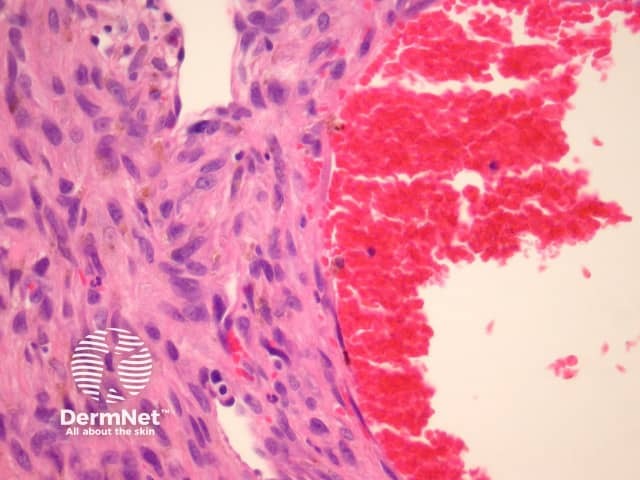

Epithelioid dermatofibroma is a well-recognised variant of dermatofibroma that may be confused with other benign and malignant mesenchymal lesions. The recent discovery of common ALK-1 translocation has led to the belief by some authorities that this is best considered a distinct entity rather than a form of dermatofibroma. Clinically it is distinctive, presenting as a polypoid red nodule. Like common dermatofibromas, epithelioid dermatofibromas are found most often on the leg. However, they can be found at unusual sites including the tongue.

Sections through epithelioid dermatofibroma show a centrally located, circumscribed tumour underlying an epidermal collarette. The tumour is composed of cells arranged in sheets and sometimes a storiform pattern. Individual cells show epithelioid morphology with abundant eosinophilic cytoplasm with round vesicular nuclei and prominent nucleoli (figures 5, 6). The cells may be markedly enlarged and display some nuclear atypia and mitoses. There is frequently an associated inflammatory cell infiltrate which can be helpful for the diagnosis.

Differential diagnosis includes other epithelioid tumours:

Figure 5

Figure 6